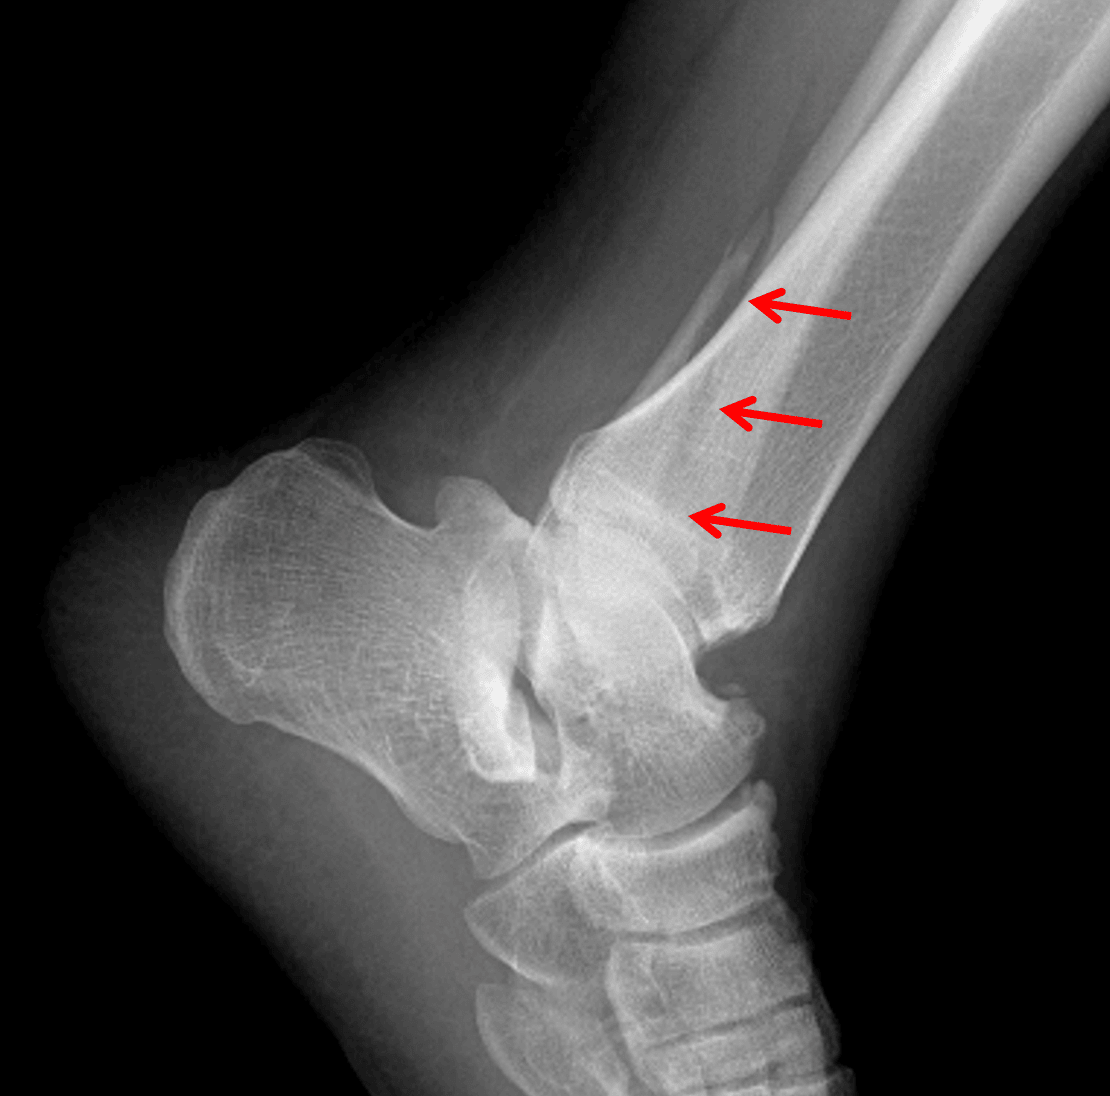

Red arrows: Weber B distal fibular fracture, which is actually best seen on the lateral view in this patient.

Acute, obliquely-oriented distal fibular fracture with inferomedial extension to the level of the tibiotalar joint (Weber B). Overlying soft tissue swelling.

• Weber type B: lateral malleolar fracture with fracture line exiting medially at the level of the talar dome – these are stable if the medial structures are intact: look for widening of the medial clear space (indicating deltoid ligament injury) and widening of the distal tibiofibular syndesmosis